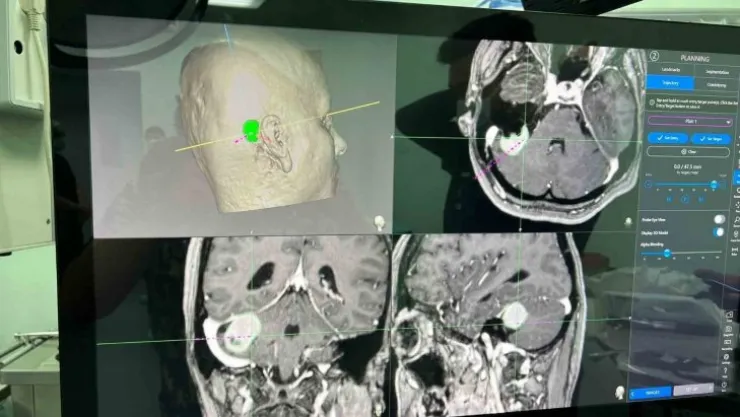

Niğde Ömer Halisdemir Üniversitesi Eğitim Araştırma Hastanesi'nde ilk defa ileri tetkik ve uygulama gerektiren köşe tümörü ameliyatı başarıyla gerçekleştirildi.

Daha önce teknik yetersizlikler nedeniyle Niğde’de yapılamayan ve hastaların başka şehirlere sevk edildiği köşe beyin tümörü ameliyatları, eksik cihazların giderilmesi ile artık Niğde’de yapılabiliyor. Baş ağrısı ve baş dönmesi şikayetleri ile hastaneye başvuran 43 yaşındaki Figen Turgut’a yapılan tetkikler sonucu köşe tümörü olarak tabir edilen kulak arkasında beyin zarından kaynaklı bir kitle tespit edildi. Yapılan tetkiklerin ardından ameliyat kararı alan Beyin Cerrahi Uzm. Op. Dr. Burak Yürük, Türkiye’de ileri merkezlerde kullanılan cihazların hastaneye alınması ile hastanın ameliyatını gerçekleştirdi. Kısa sürede sağlığına kavuşan ve yarın taburcu olması beklenen hastayı Başhekim Dr. Öğretim Üyesi Yakup Çetinkaya ziyaret etti.

Operasyonu gerçekleştiren Beyin ve Sinir Cerrahi Uzmanı Op. Dr. Burak Yürük de, "Burada bir takım eksik teknik imkanları sağlamak adına bunun planlamasını yaptık. Türkiye’de birçok ileri merkezde olan dediğimiz cihazları kullanarak ameliyatın daha güvenli olmasını sağladık. Daha sonrasında hastanın bir takım ameliyat öncesi tetkiklerini yaptık. Bunlar Türkiye’de ileri merkezlerde olan tetkikler. Hastanın ameliyattan sonra bu tür ameliyatlarda korktuğumuz birtakım sinir yaralanmaları olur ve biz böyle bir yaralanmayla karşılaşmadık konforu arttırıcı cihazların yardımıyla" dedi.

Beyin zarından kaynaklı tümörü olan hastanın 1 gün yoğun bakımda kaldığını, yarın da taburcu edileceğini söyleyen Op. Dr. Burak Yürük, "Bu ameliyatın daha konforlu, güvenli olması için yüze, yanağa ve dile giden sinirleri montize ettik. Görüntülemesini yaptık. Aynı zamanda ince kesik tetkiklerini elde ederek hem ameliyat sırasında, hem ameliyat sonrasında bize yol gösterici navigasyon dediğimiz bir haritalama yaparak tümörün tamamına yakınını boşalttık. Ameliyat sonrası filminde de hasta, mevcut baskı oluşturacak bir kitle lezyonu artık göstermiyor" diye konuştu.